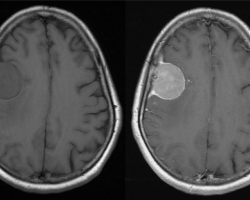

Méningiome